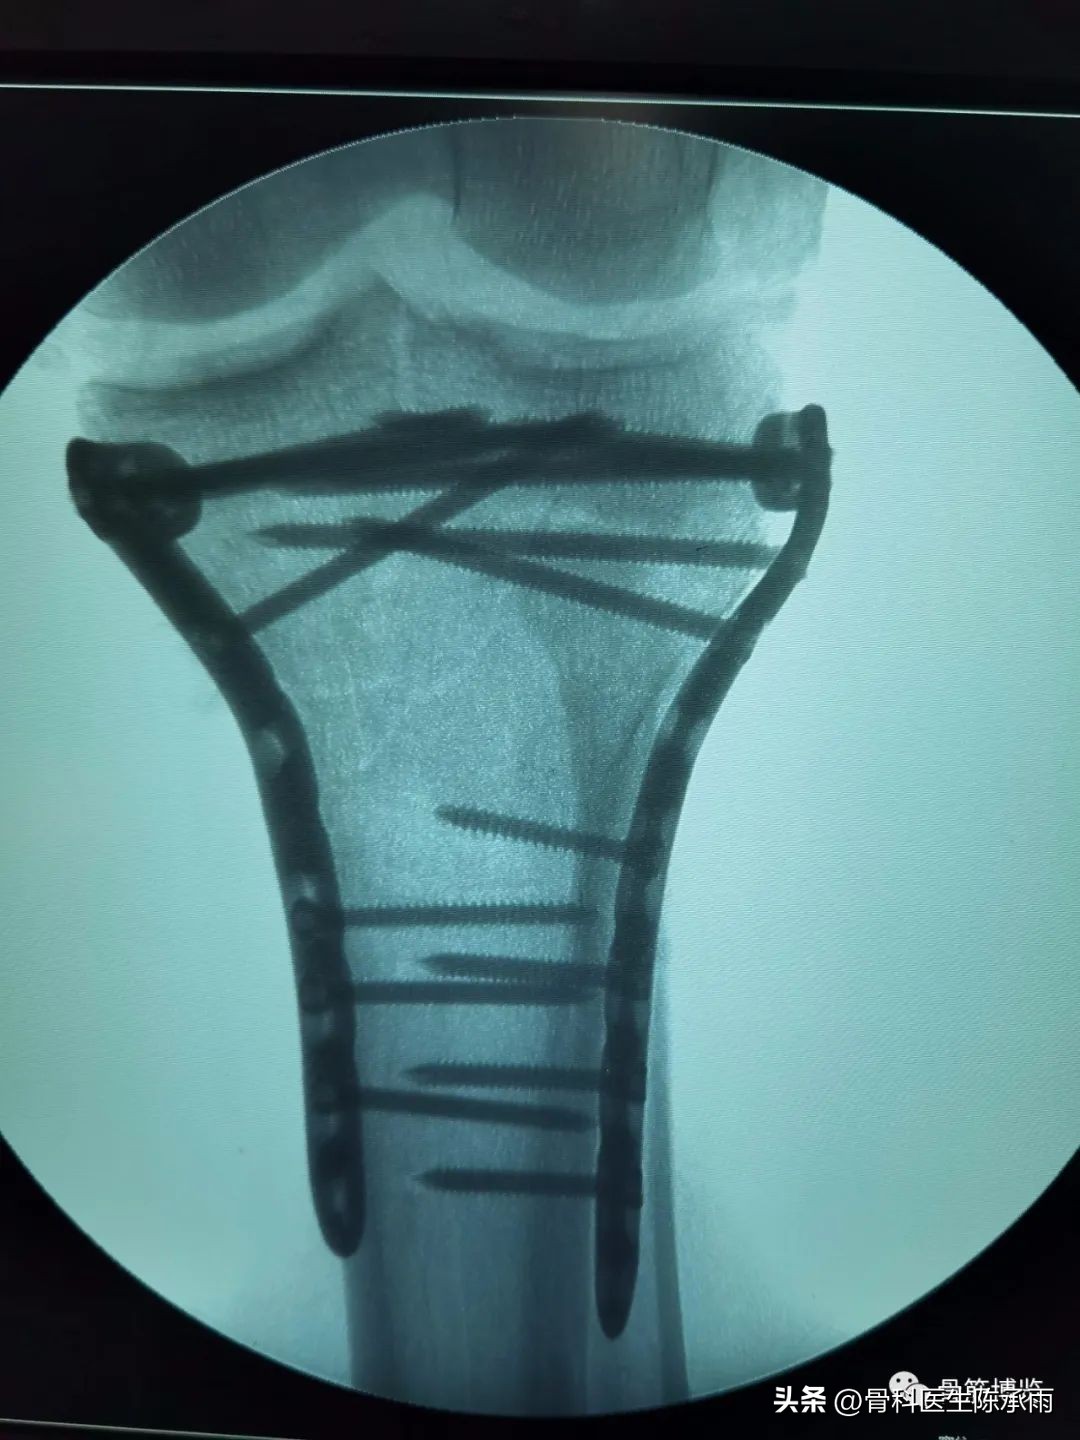

近段时间的胫骨平台骨折,没来得及详细整理

郓城县人民医院骨科诊疗技术飞速提升,开通了创伤中心绿色通道。现年手术病人达到1500余例,除常规手术外,微创手术迅速发展。关节镜,椎体成形,股骨粗隆闭合复位固定,髋膝关节置换,脊柱等手术在全市处于领先水平。